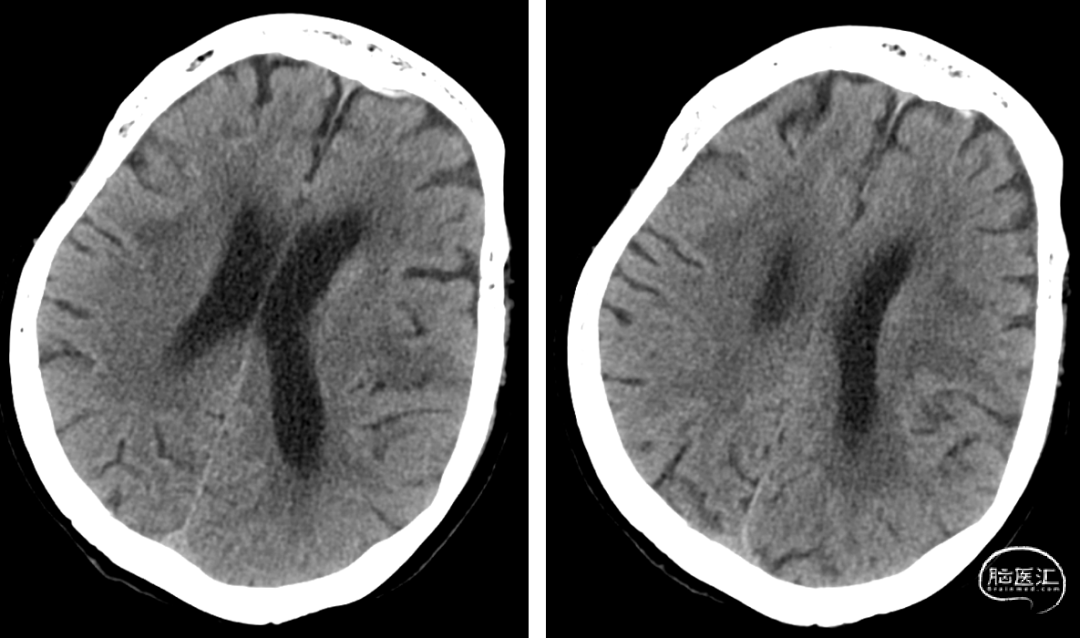

患者入院后(2-22 21:30PM)症状加重,部分混合型失语,右上肢肌力0级,右下肢肌力3级,右侧鼻唇沟变浅,NIHSS评分12分。(急诊CTP)。

患者老年女性,既往心房颤动病史。因“言语障碍及右侧肢体乏力29小时”入院。患者有明确的大血管闭塞,入院后患者症状加重,MRA提示左侧大脑中动脉闭塞,考虑进展性卒中,患者急诊CTP评估后考虑缺血半暗带大有血管内治疗指征,排除禁忌,拟急诊手术治疗。